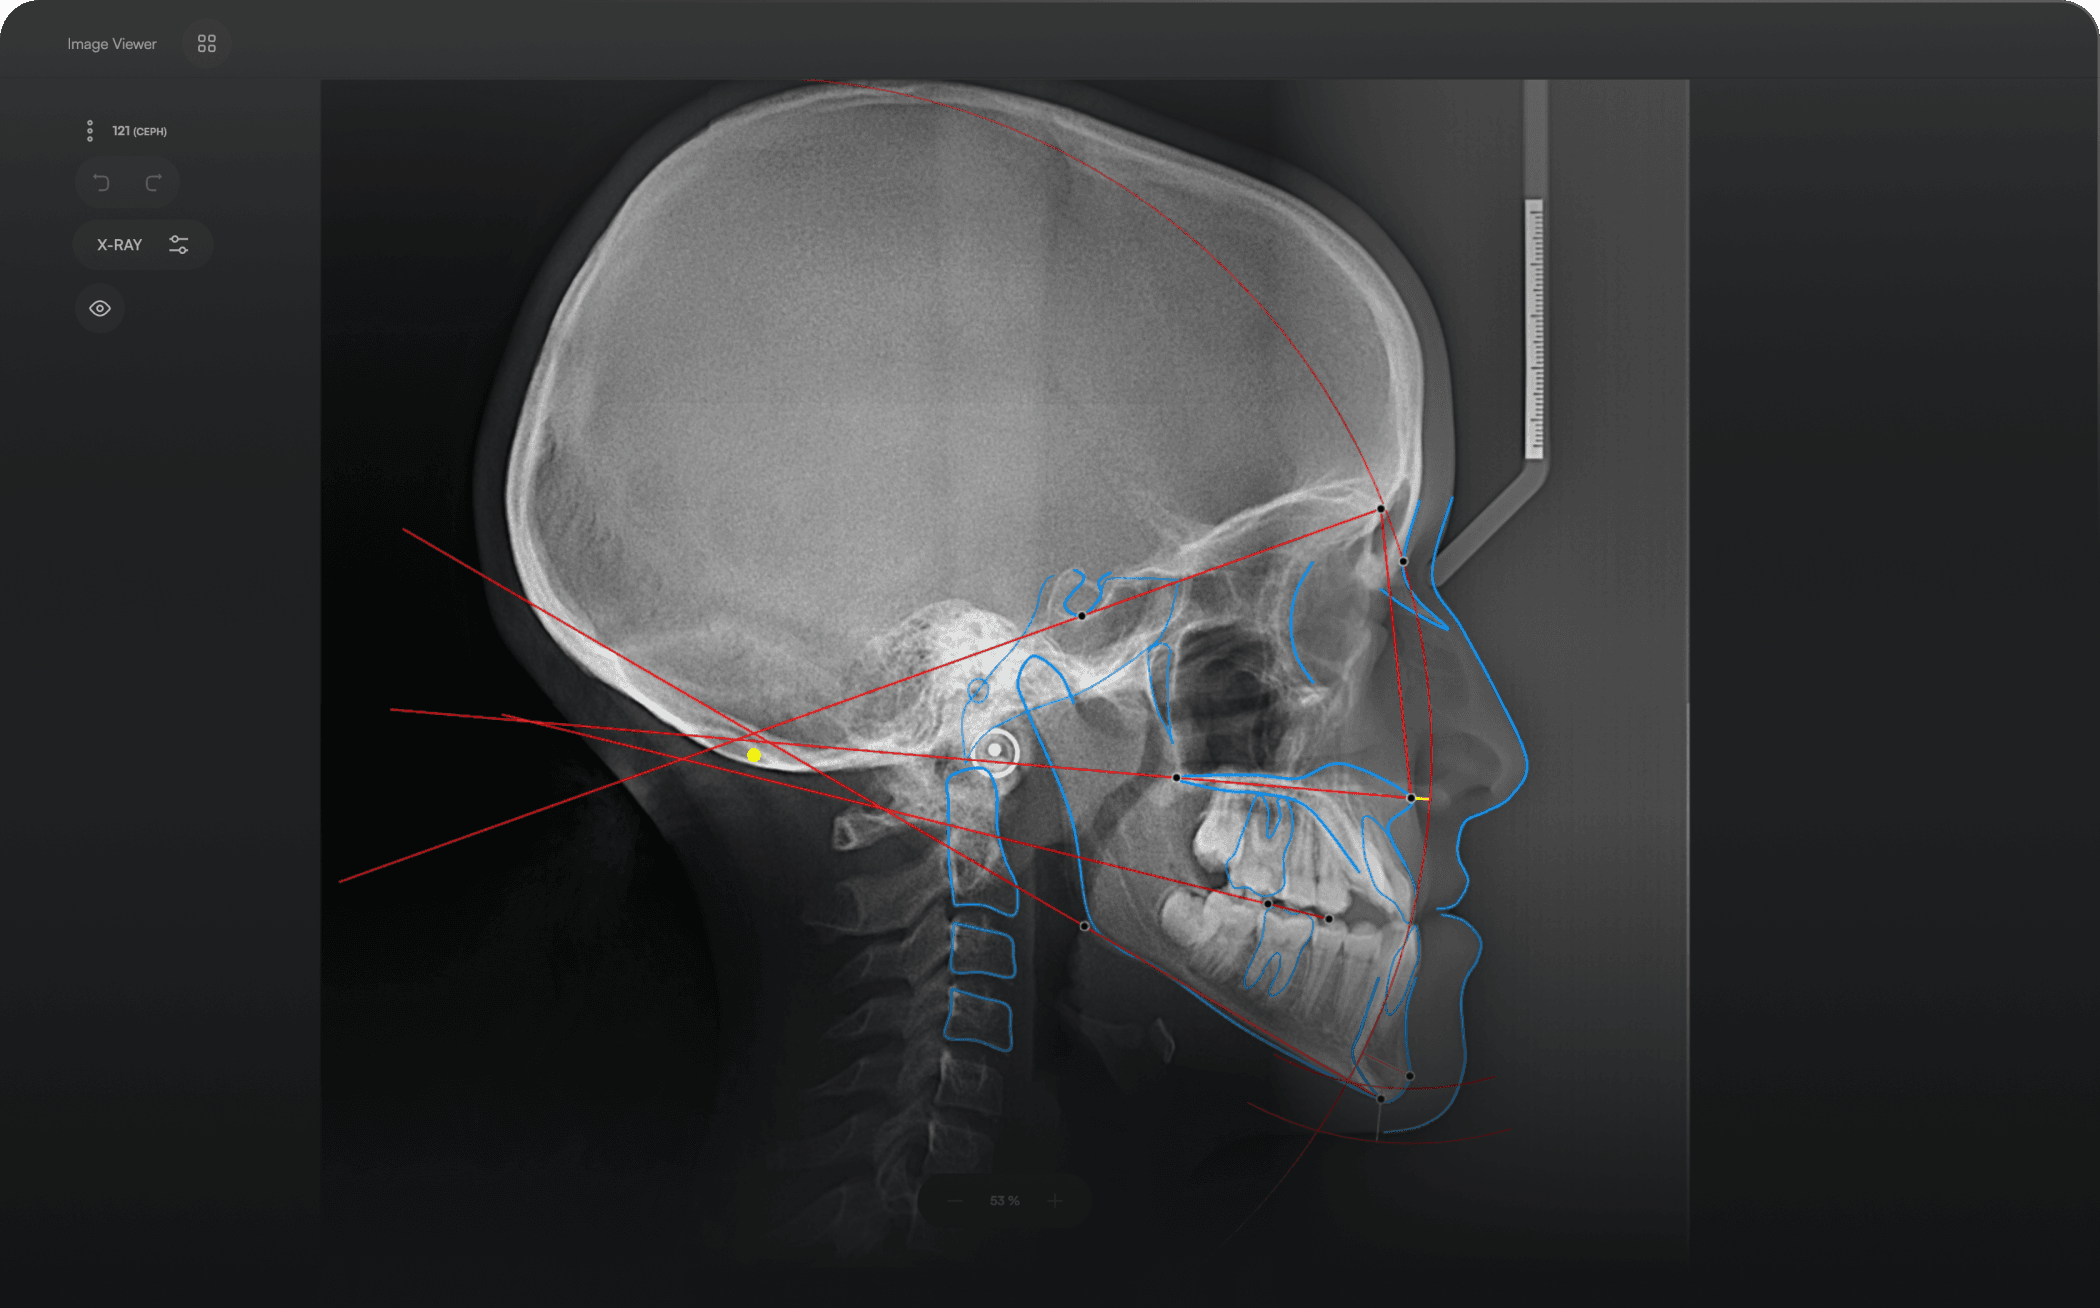

Unparalleled Speed

Identify 150+ orthodontic landmarks in under 10 seconds — a task that

traditionally may take more than 30 minutes.

Accurate and Consistent. Our high-precision AI technology ensures identical outcomes every time. quality.

Clinically Proven. Backed by research papers demonstrating speed and accuracy